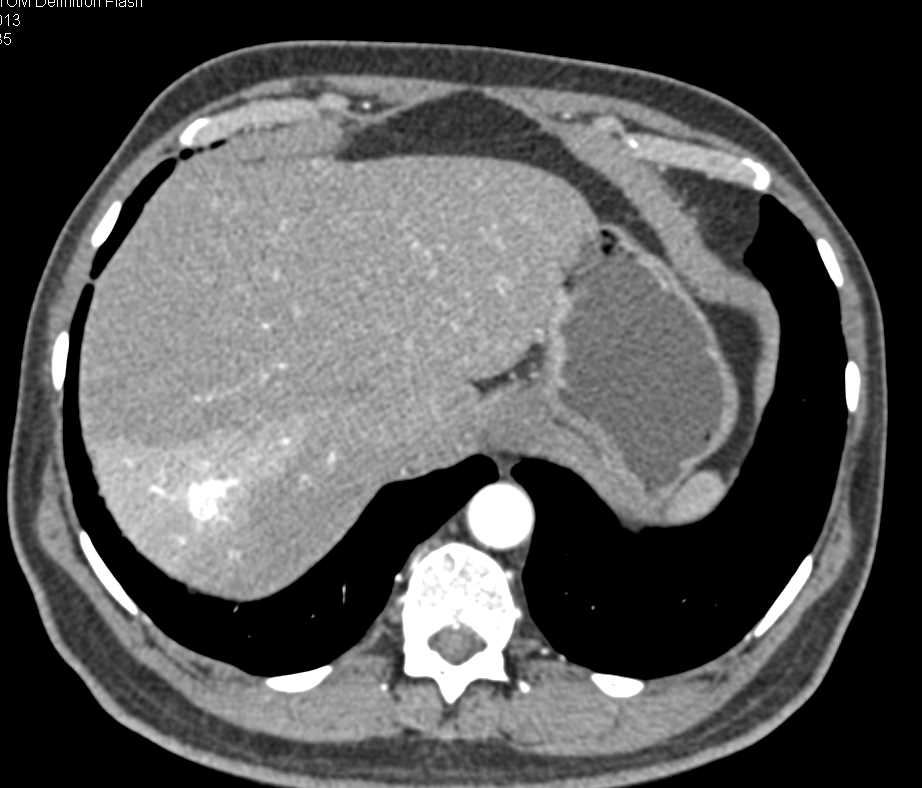

Cirrhosis with Clot in the Portal Vein